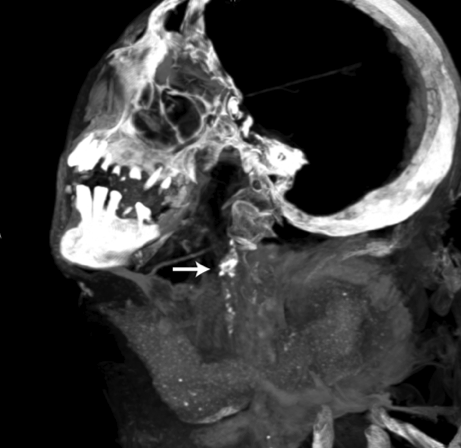

A U.S.-Egyptian research team has uncovered the earliest documented case of coronary atherosclerosis in a princess who died in her early 40s and lived between 1580 and 1550 B.C. Of the other mummies studied – a sampling of the elite in ancient Egypt – almost half showed evidence of atherosclerosis in one or more of their arteries, calling into question our perception of atherosclerosis as a modern disease, according to research presented this week at the American College of Cardiology (ACC) Scientific Session in New Orleans.

While atherosclerosis has been observed before in ancient Egyptians, this study found it to be more prevalent than previously thought. The interdisciplinary team performed whole body computerized tomography (CT) scans on 52 ancient Egyptian mummies to determine if atherosclerosis was present. Of the 44 with identifiable arteries or hearts, nearly half (45 percent) had calcifications either in the wall of an artery or along the course of an artery that are diagnostic of or highly suggestive of atherosclerosis. “Commonly, we think of coronary artery or heart disease as a consequence of modern lifestyles, mainly because it has increased in developing countries as they become more westernized,” said Gregory S. Thomas, M.D., MPH, clinical professor and director of nuclear cardiology education, University of California, Irvine and the study’s co-principal investigator.

“These data point to a missing link in our understanding of heart disease, and we may not be so different from our ancient ancestors.” Most of the atherosclerosis was found in the large arteries of the body, including the aorta in the abdomen. However, key smaller arteries were also involved. About 7 percent of the mummies had obstructions in the heart arteries, and 14 percent had blockages in the arteries to the brain, the carotid arteries, which is a leading cause of stroke in the present day. Researchers also found that, similar to now, advancing age was highly predictive of the presence and severity of atherosclerosis.

Thomas explains that the calcific atherosclerosis seen with CT scanning looks just like the atherosclerosis of today and appears in the same locations. While researchers could not determine the exact cause of death in these mummies, symptoms consistent with cardiac chest pain had been described in ancient Egyptian scrolls. In order to understand the lifestyles of ancient Egypt’s elite, the team of researchers worked with Egyptologists to review risk factors that might affect the health of the heart and arteries.